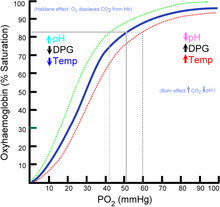

Hypoxemia – is a condition involving abnormally low blood oxygen levels. It can lead to bluish skin, difficulty breathing and fast heart rate. Apart from sleep apnea and higher altitudes, hypoxemia can be also be caused by many underlying illnesses, mainly lung and heart related especially in conditions of low environmental oxygen, diffusion impairment, hypoventilation, right -to left atrial shunting (image below).

Hypoxia – is a condition involving abnormally low levels of oxygen in body tissues. It can lead to bluish skin, confusion, difficulty breathing, restlessness and fast heart rate. Hypoxia is different to hypoxemia as hypoxia is low oxygen levels in tissues whereas hypoxemia is low oxygen levels in blood.

Hypercapnea – is also known as hypercarbia. It is a condition related to high carbon dioxide levels in the body. Carbon-dioxide can get built up in the blood if the body doesn’t successfully get rid of it within time. Conditions that either increase the levels of carbon-dioxide in the body or prevent the waste carbon-dioxide from getting to the lungs and discarded are usually the main causes of hypercapnea. Illnesses related to lung, brain, muscles and nerves are usually the most common causes. Hypercapnia is different to hypoxemia as hypercapnia is the condition with high carbon-dioxide levels in blood whereas hypoxemia is low oxygen levels in blood.

Respiratory failure is a critical condition that develops due to low blood-oxygen levels in the bloodstream that makes involuntary tasks like breathing almost impossible to do on your own. The low blood-oxygen levels results due to inadequate gas exchange during pulmonary circulation, which could be because of pump failure or lung failure. Pump failure is a ventilation failure which causes hypercapnia whereas lung failure is gas exchange failure causing hypoxemia. It can also de defined as arterial oxygen tension (Pao2 < 60mmHg) or arterial carbon dioxide tension (PaCO2).

Type I: – involves a ventilation/perfusion mismatch that causes untreatable hypoxemia (PaO2). Another characteristic of type I respiratory failure is alveolar flooding.

Type II: – involves alveolar hypoventilation resulting in hypercapnia (PaCO2). There is a significant reduction in the alveolar minute ventilation that entails inadequate removal of carbon dioxide.

- Arterial Blood Gas – this test can be done for quantifying the severity of the respiratory failure or measuring the oxygen concentration in the blood to test for hypoxia severity.